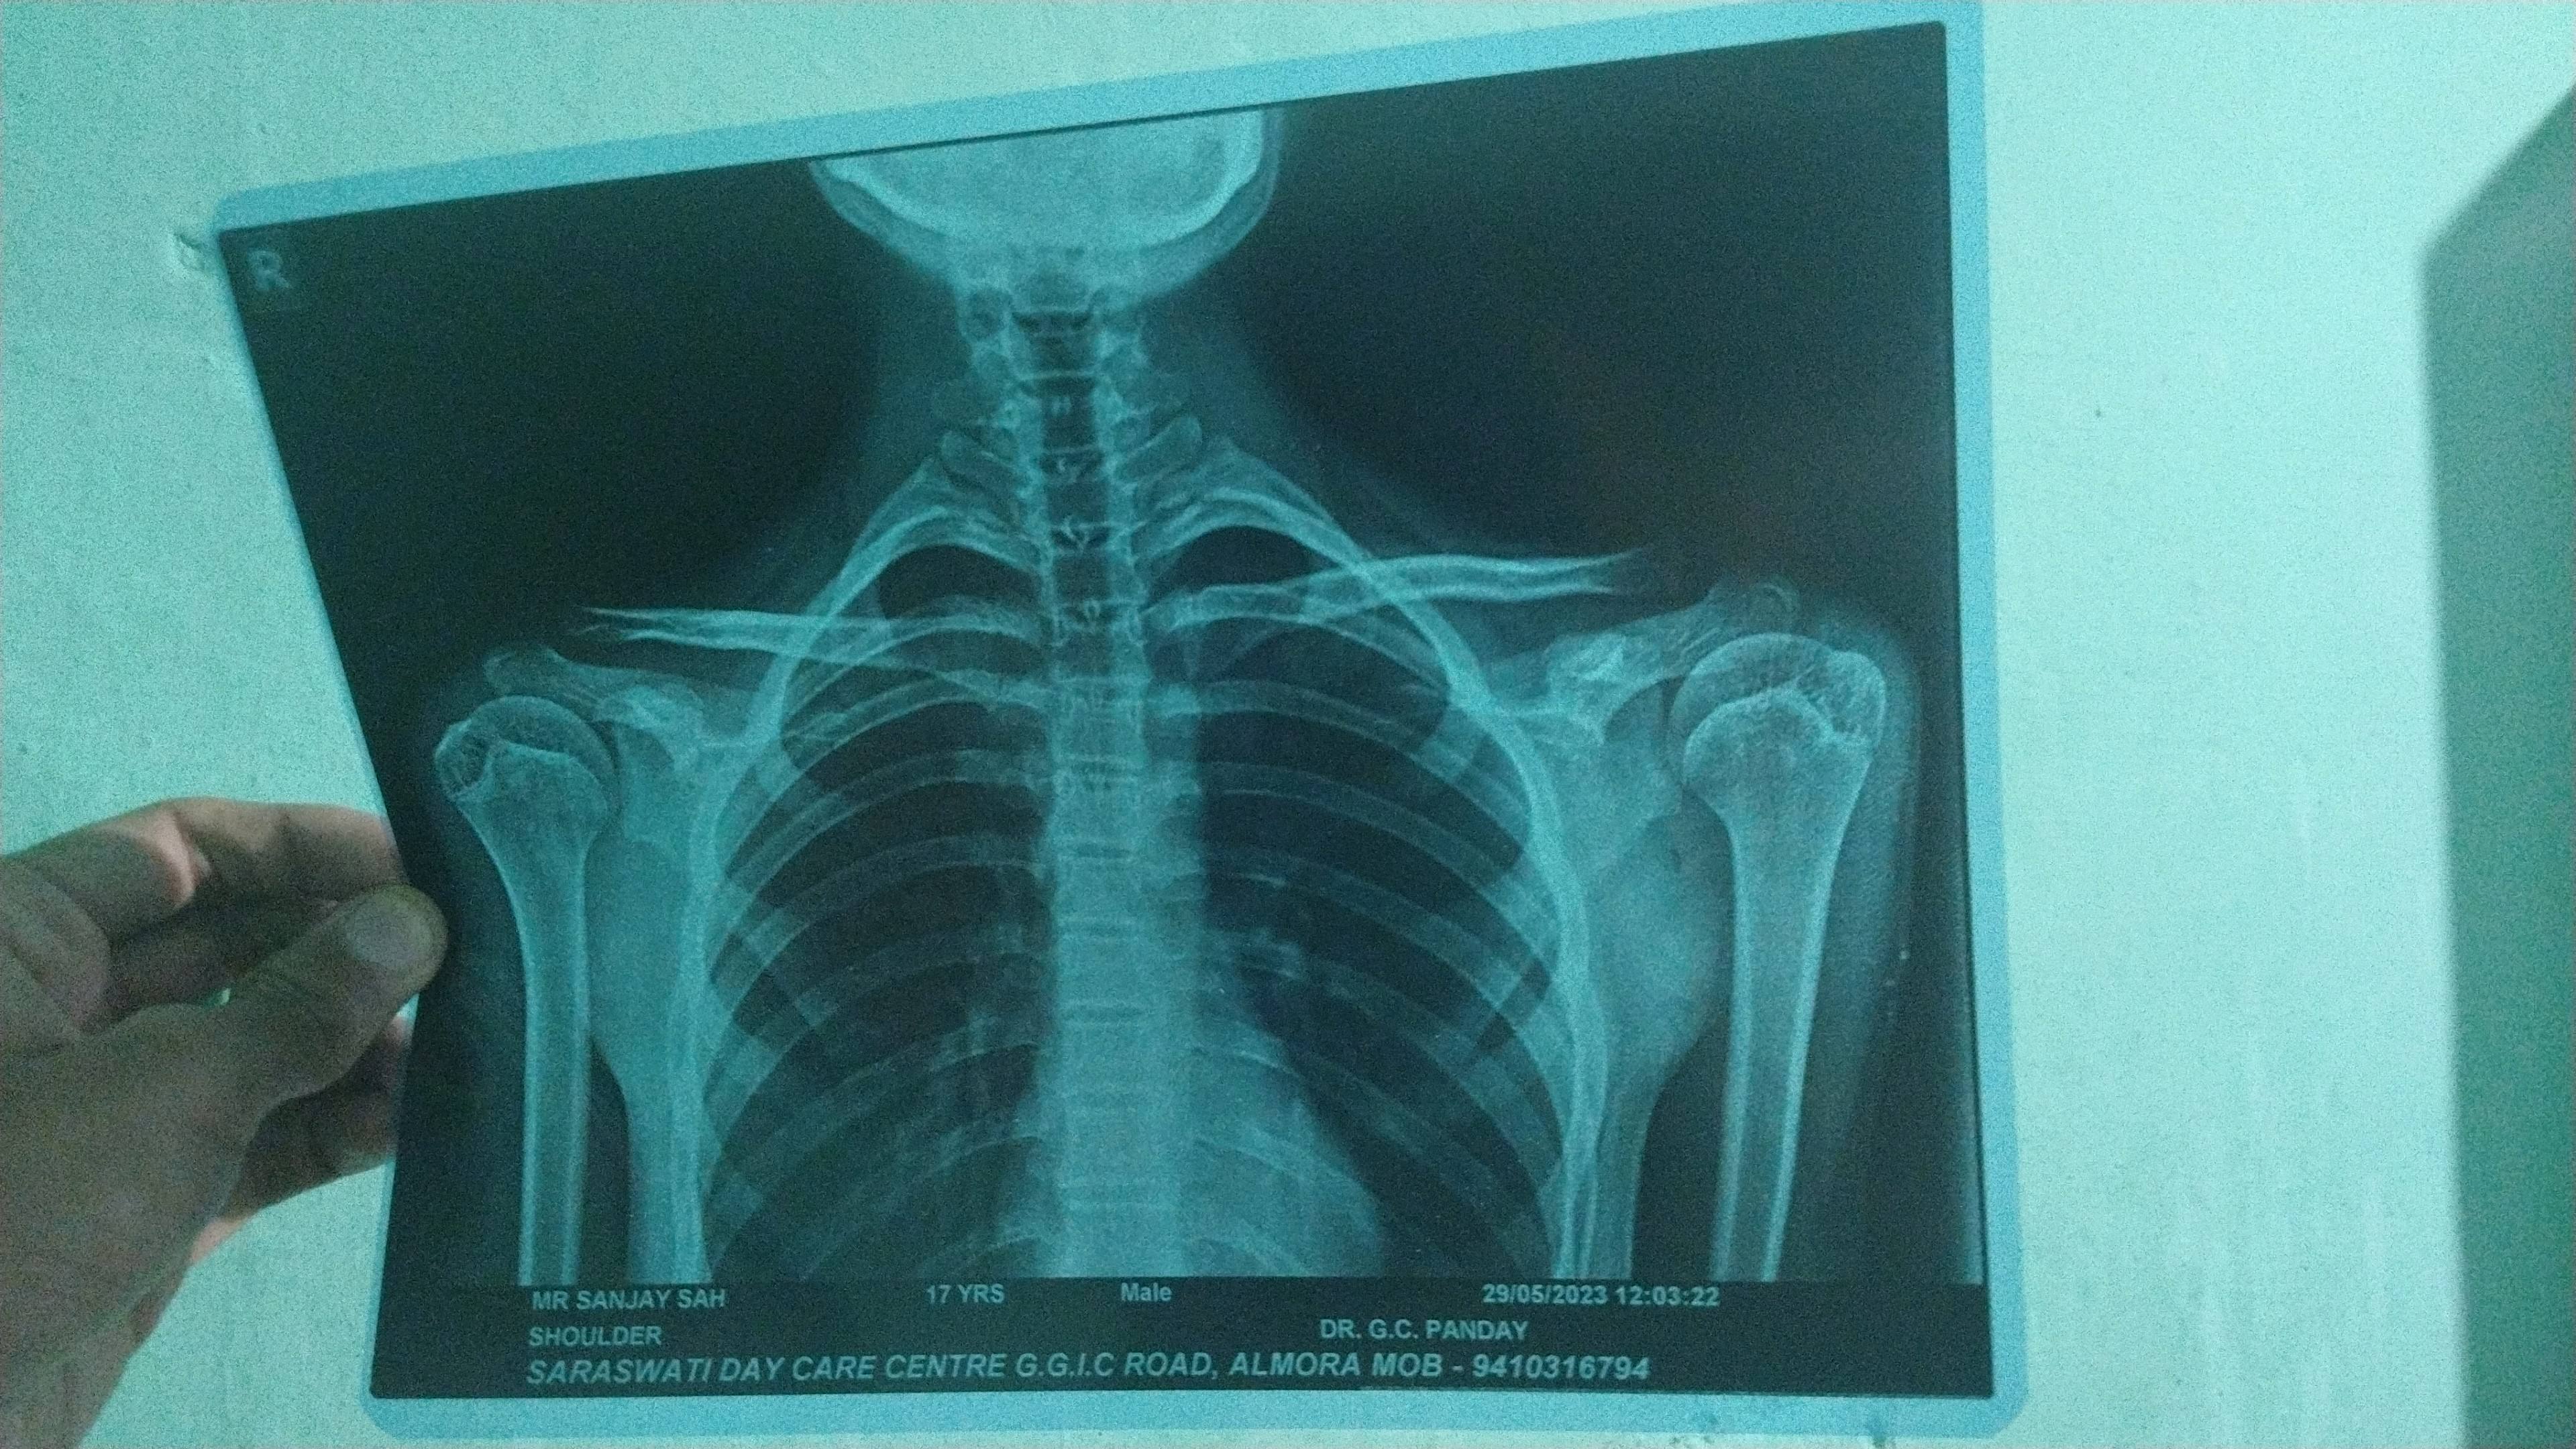

I have pain in my left shoulder Can you find out what's the problem ?

Here are x-rays of 2 different dates and inform me after complete

reason of accident (Fallen From Tree)